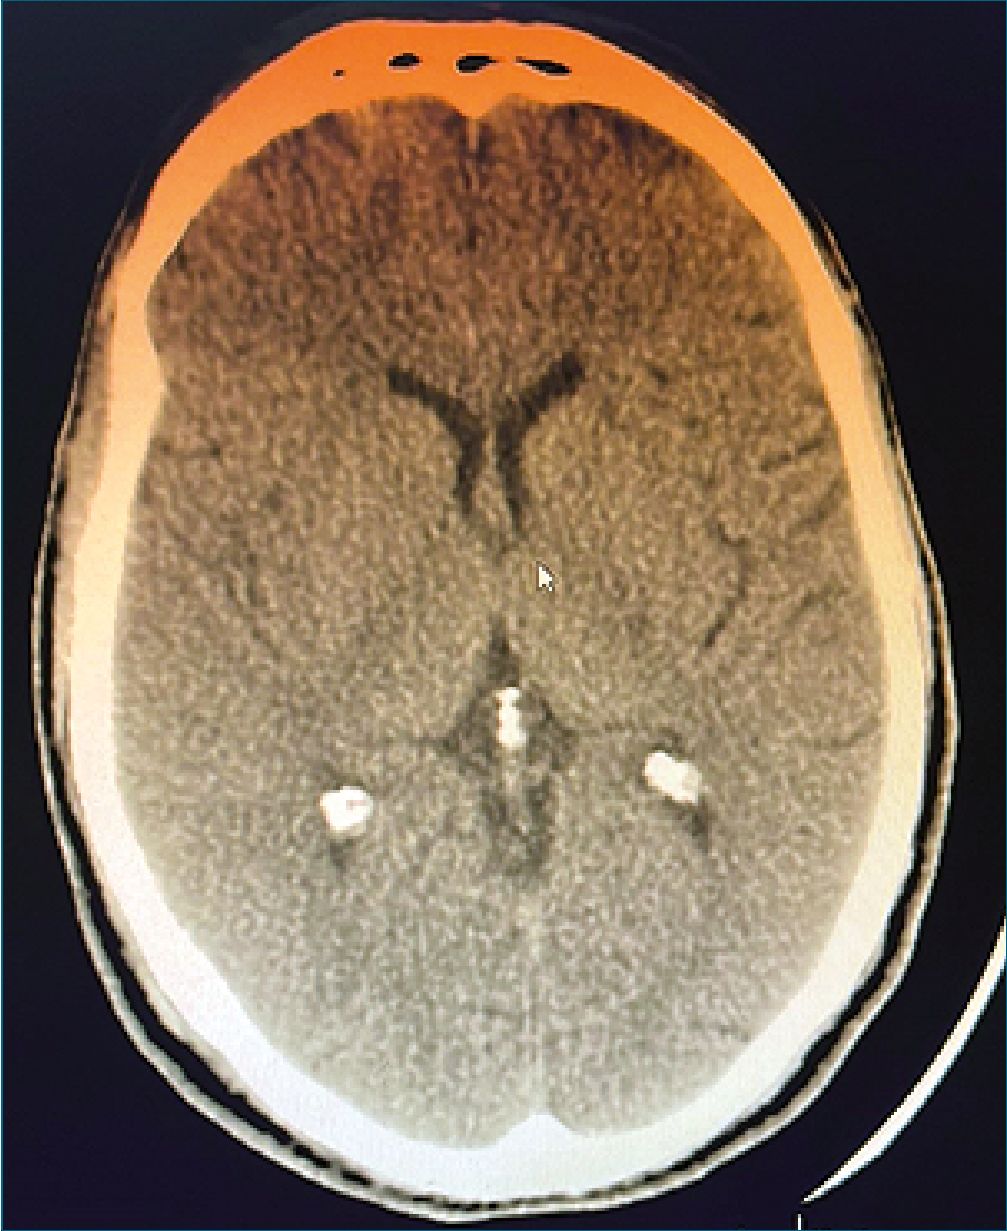

Figura 1. AngioTAC posoperatorio inmediato de mediastinoscopia.

Extubación en block, paciente con ventilación espontánea con adecuado esfuerzo inspiratorio, cumpliendo órdenes. Paciente con tendencia al sueño, es trasladado a sala de recuperación anestésica. Inmediatamente, se revalora constatándose, hemiplejia izquierda, y parálisis facial central izquierda. Se realizó angioTAC cerebral y de vasos de cuello. Del informe se destaca: ausencia de signos tempranos de isquemia, ni áreas configuradas, sin hematomas del parénquima, hemorragia subaracnoidea ni sangrado intraventricular. Se identificó defecto en el relleno de carótida primitiva que podría corresponder a disección, y a nivel de cerebral media derecha en su sector M1 se observó defecto compatible con trombo embólico por contexto clínico del paciente (Figura 1).